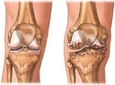

Kireçlenme Nedir?Kireçlenme, tıpta "osteoartrit" olarak adlandırılan bir durumdur ve eklemlerde kireç veya kalsiyum birikmesi sonucu oluşan dejeneratif bir hastalıktır. Bu durum, eklem kıkırdağının aşınmasına ve eklem yüzeylerinin sertleşmesine yol açarak, hareket kısıtlılığı ve ağrıya neden olur. Kireçlenme, genellikle yaşla birlikte artış gösterir ancak genetik, obezite ve eklem yaralanmaları gibi birçok faktör de bu durumu tetikleyebilir. Kireçlenmenin BelirtileriKireçlenme belirtileri genellikle yavaş bir şekilde gelişir ve zamanla şiddetlenebilir. Aşağıdaki belirtiler, kireçlenme ile ilişkili yaygın bulgulardır:

Kireçlenmenin TeşhisiKireçlenme teşhisi genellikle fiziksel muayene ve görüntüleme yöntemleriyle konur. Doktor, hastanın semptomlarını değerlendirir ve eklem hareketliliğini test eder. Ayrıca, röntgen veya manyetik rezonans görüntüleme (MRG) gibi yöntemler kullanarak eklemlerdeki değişiklikleri gözlemleyebilir. Kireçlenme Tedavi YöntemleriKireçlenme tedavisi, hastalığın şiddetine ve bireyin genel sağlık durumuna bağlı olarak değişiklik gösterebilir. Tedavi yöntemleri arasında: